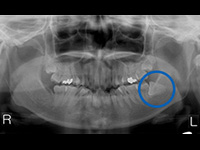

水平に埋まっている親知らずの抜歯の症例

水平に埋まった親知らずの抜歯は、頻度が高い手術です。

左下の親知らずが、水平に埋まっています。